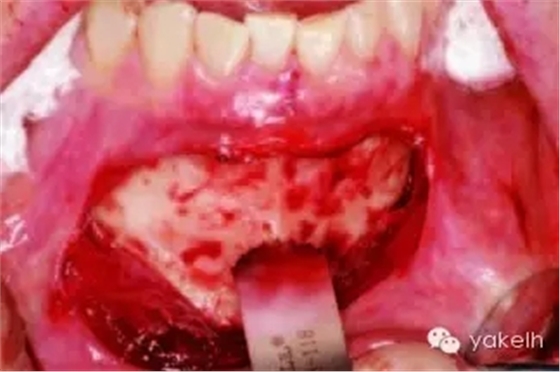

¤¤暴露頦部后,設(shè)計(jì)取骨的切口。取骨塊的大小由受區(qū)所需的骨量決定。骨切開處距離根尖以及頦孔最少應(yīng)有5mm。多數(shù)情況下,要保留下頜骨下緣以及舌側(cè)皮質(zhì)骨的完整性。唇側(cè)皮質(zhì)較厚,其內(nèi)側(cè)的松質(zhì)骨通常較致密??梢允褂脺u輪手機(jī)碳合金裂鉆(557號(hào)或701號(hào))或者來復(fù)鋸將骨切開(圖13.19)。切透皮質(zhì)骨達(dá)松質(zhì)骨后,用骨鑿將骨塊移除(圖13.20)。用單面鑿沿著骨切開線輕輕敲擊,除了下頜骨下緣,將骨塊從基底部折斷。在中線處時(shí),也可將塊狀骨分割成矩形骨塊,分段獲取。分成兩個(gè)骨塊后更容易獲取,因?yàn)榭梢杂霉氰弻⒌诙K骨塊從舌側(cè)撬起。另外,移除塊狀骨后,還可使用骨刮匙、鑿子、咬骨鉗、環(huán)形鉆獲取

一些松質(zhì)骨,但是松質(zhì)骨的量十分有限。在移除塊狀骨后,可以將止血材料如膠原或明膠海綿置于松質(zhì)骨表面。當(dāng)獲取較大的骨塊時(shí),供區(qū)應(yīng)使用骨替代材料如羥基磷灰石,來維持唇側(cè)的外形(圖13.21)。較少或者顆粒狀的骨移植時(shí),可使用環(huán)形鉆、骨收集器、骨挖器來獲取。把骨塊植入受區(qū)后,再將供區(qū)的傷口縫合,這可以縮短取骨與植骨之間的時(shí)間。分離前庭溝切口上方的黏膜,以減少水腫和下唇運(yùn)動(dòng)所產(chǎn)生的張力。用可吸收縫線分層縫合前庭溝切口(圖13.22)。深層組織使用4-0可吸收線縫合,表層黏膜使用4-0鈷腸線縫合。術(shù)后使用壓力繃帶包扎頦部,以減少水腫、血腫形成及切口裂開(圖13.23)。

圖13.19 用矢狀鋸行頦部骨切開。

圖13.20 從頦部獲取厚的皮髓質(zhì)骨塊。